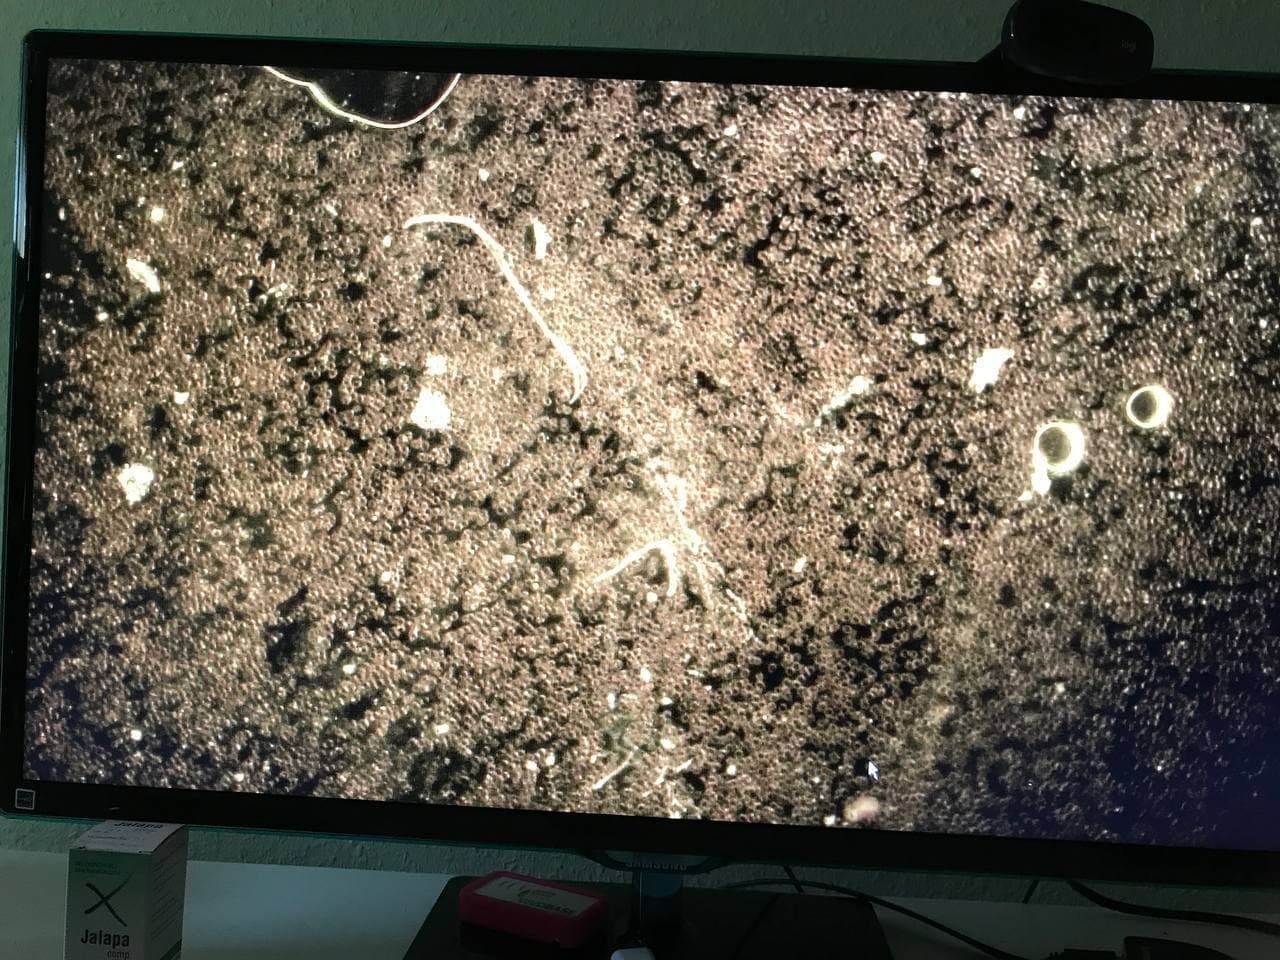

GENimpfschaden

im Blutbild einer GENgeimpften Person

15.9.2021: 9 Fotos

Impfschäden Schweiz

Coronaimpfung, [15.09.21 13:19]

https://t.me/Impfschaden_Corona_Schweiz/21521

[Weitergeleitet aus Holger Fischer

Rechtsanwalt (Maya Stella)]

Im folgenden wieder Blutbilder von Blut von

Geimpften, mit Verunreinigungen

(Dunkelfeldmikroskopie) |

GENimpfschaden

im Blutbild 15.9.2021: Foto 1

Impfschäden Schweiz Coronaimpfung, [15.09.21

13:19]

https://t.me/Impfschaden_Corona_Schweiz/21522

[Weitergeleitet aus Holger Fischer Rechtsanwalt

(Maya Stella)]

Scheibenartiges Gebilde mit leuchtenden Punkten

GENimpfschadne im Blutbild 15.9.2021: Foto 1

[37] |

GENimpfschaden

im Blutbild 15.9.2021: Foto 2

Impfschäden Schweiz Coronaimpfung, [15.09.21

13:19]

https://t.me/Impfschaden_Corona_Schweiz/21523

[Weitergeleitet aus Holger Fischer Rechtsanwalt

(Maya Stella)]

Scheibenartige Form mit Spike Proteinen (?)

GENimpfschaden im Blutbild 15.9.2021: Foto 2

[38]

|

GENimpfschaden

im Blutbild 15.9.2021: Foto 3

Impfschäden Schweiz Coronaimpfung, [15.09.21

13:19]

https://t.me/Impfschaden_Corona_Schweiz/21524

[Weitergeleitet aus Holger Fischer Rechtsanwalt

(Maya Stella)]

Seltsame Form über den Erys

GENimpfschaden im Blutbild 15.9.2021: Foto 3

[39] |

GENimpfschaden

im Blutbild 15.9.2021: Foto 4

Impfschäden Schweiz Coronaimpfung, [15.09.21

13:19]

https://t.me/Impfschaden_Corona_Schweiz/21525

[Weitergeleitet aus Holger Fischer Rechtsanwalt

(Maya Stella)]

Seltsame Form im Blut Erys wirken wie tot

GENimpfschaden im Blutbild 15.9.2021: Foto 4

[40] |

GENimpfschaden

im Blutbild 15.9.2021: Foto 5

Impfschäden Schweiz Coronaimpfung, [15.09.21

13:19]

https://t.me/Impfschaden_Corona_Schweiz/21526

[Weitergeleitet aus Holger Fischer Rechtsanwalt

(Maya Stella)]

Stechapfelformen

GENimpfschaden im Blutbild 15.9.2021: Foto 5

[41] |

GENimpfschaden

im Blutbild 15.9.2021: Foto 6

Impfschäden Schweiz Coronaimpfung, [15.09.21

13:19]

https://t.me/Impfschaden_Corona_Schweiz/21527

[Weitergeleitet aus Holger Fischer Rechtsanwalt

(Maya Stella)]

spitze Gebilde

GENimpfschaden im Blutbild 15.9.2021: Foto 6

[42]

|

GENimpfschaden

im Blutbild 15.9.2021: Foto 7

Impfschäden Schweiz Coronaimpfung, [15.09.21

13:19]

https://t.me/Impfschaden_Corona_Schweiz/21528

[Weitergeleitet aus Holger Fischer Rechtsanwalt

(Maya Stella)]

Unbekanntes Objekt im Blut

GENimpfschaden im Blutbild 15.9.2021: Foto 7

[43]

|

GENimpfschaden

im Blutbild 15.9.2021: Foto 8

Impfschäden Schweiz Coronaimpfung, [15.09.21

13:19]

https://t.me/Impfschaden_Corona_Schweiz/21529

[Weitergeleitet aus Holger Fischer Rechtsanwalt

(Maya Stella)]

unnatürliche Form

GENimpfschaden im Blutbild 15.9.2021: Foto 8

[44] |

GENimpfschaden

im Blutbild 15.9.2021: Foto 9

Impfschäden Schweiz Coronaimpfung, [15.09.21

13:19]

https://t.me/Impfschaden_Corona_Schweiz/21530

[Weitergeleitet aus Holger Fischer

Rechtsanwalt (Maya Stella)]

vermehrt hell leuchtende Gebilde

GENimpfschaden im Blutbild 15.9.2021: Foto 9

[45] |

GENimpfschaden Blut nach GENimpfung Schweiz

6.11.2021: Verklebte Blutkörperchen und Gegenstände im

Blut

Impfschäden Schweiz Coronaimpfung, [06/11/2021 03:17 P.M.]

https://t.me/Impfschaden_Corona_Schweiz/28793

Diese Dunkelfeld-Bilder wurden am 28.09.2021 vom Blut eines

18 jährigen Mannes aufgenommen, der 10 Tage zuvor die erste

Dosis mit Biontech/Pfizer bekommen hatte. Sie zeigen

Anomalien, die die Untersuchende (Name ist Kanalbetreiberin

bekannt) laut ihrer Aussage in ihrer langen Zeit der Praxis

noch nie zuvor gesehen hat. Auch derjenige, der die Bilder

direkt vom Bildschirm abfotografiert hat, ist pers. bekannt.